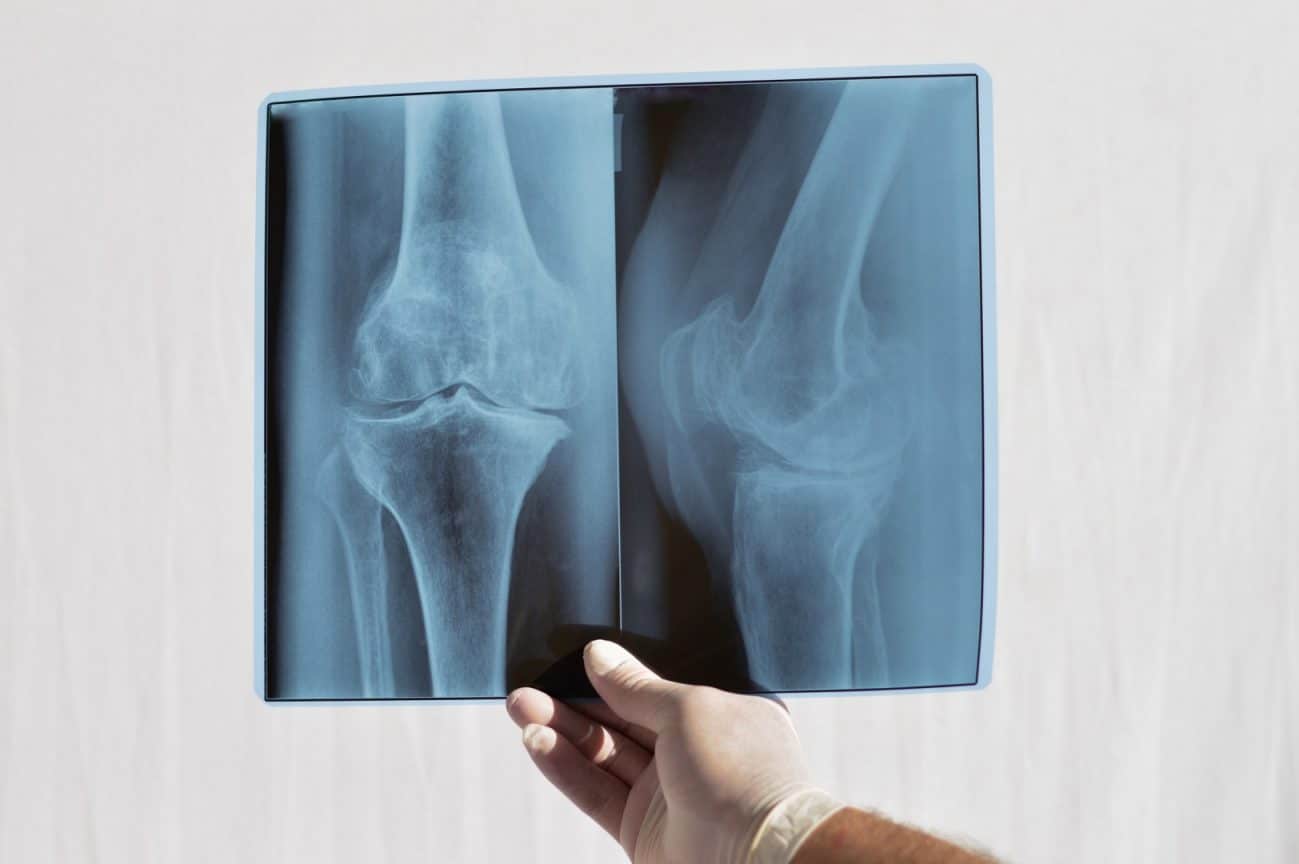

Genunchiul este una dintre cele mai mari și complexe articulații ale corpului nostru. Imaginează-ți că genunchii funcționează precum balamalele. Ei au capacitatea de a susține greutatea corpului în timpul mersului. Cu ajutorul lor, poți realiza mișcările zilnice de bază: ridicat, alergat și mers. Oasele care alcătuiesc articulațiile genunchiului sunt: rotula, femurul, tibia și fibula. În momentul în care ceva nu funcționează la parametrii normali, se recomandă radiografia de genunchi.

Fiind niște părți extrem de complexe ale corpului tău, capetele osoase din genunchi sunt acoperite cu un strat foarte neted de cartilaj articular. Cartilajele de acest fel favorizează mișcarea. Altfel spus, ca aceste cartilaje să fie protejate, există niște meniscuri care preiau șocurile transmise în articulație. În cazul în care anumite părți ale genunchiului sunt afectate, este nevoie de radiografia de genunchi.

După efectuarea unui examen clinic, medicul îți va recomanda o radiografie simplă sau un RMN pentru diagnosticarea corectă. Radiografia de genunchi este esențială pentru a cântări și depista uzura și pierderea cartilajului în zona aceea. Aceste simptome sunt asociate afecțiunii de artroză a genunchiului. În cazul unei artroze diagnosticate, radiografia de genunchi poate să îi arate medicului prezența osteofitelor, chisturilor sau deformărilor. Pentru o evaluare mai complexă ți se va recomanda un examen RMN.

Radiografia de genunchi și celelalte investigații de radiologie și imagistică medicală sunt efectuate în afecțiuni ortopedice. Printre ele se numără luxațiile, fracturile sau identificarea unor afecțiuni la nivelul oaselor sau articulațiilor. La radiografie sector 3 pot fi accesate aproximativ 50 de tipuri de radiografii. Acestea sunt efectuate și interpretate de un medic radiolog cu o vastă experiență.